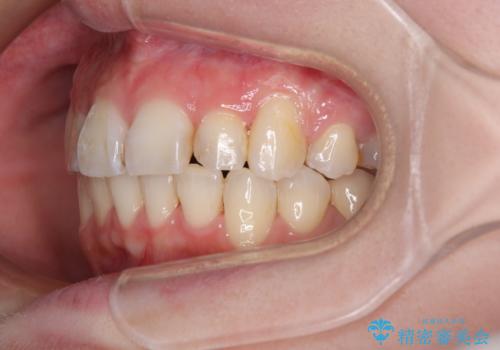

- 前歯のデコボコを気にして来院された患者様です。

上下の前歯にデコボコがあり、更にはディープバイトにより下顎前歯の大半が隠れている状態でした。

上顎左右第一小臼歯の2本を抜歯し、ワイヤー装置を使用して咬み合わせ高さを改善しながら、歯列を整えて行くこととしました。